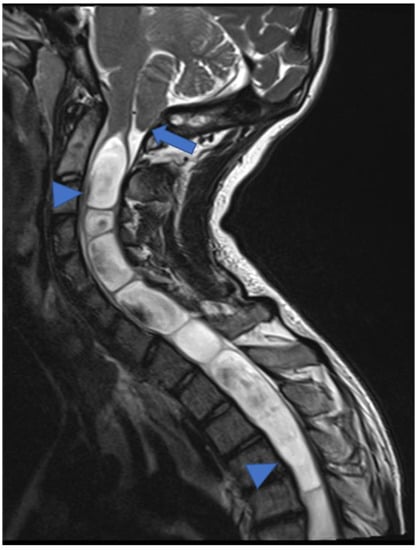

2.1. Gliomas